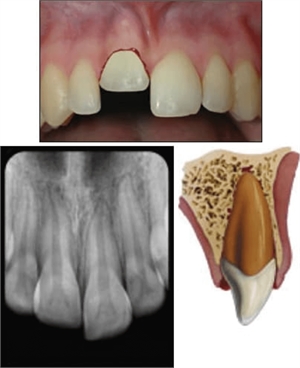

Dental intrusion - facial and occlusal view. How the intruded tooth looks on a dental x-ray

Tooth socket intrusion - dental intrusion

Dental intrusion is forceful invading the socket of the tooth by the tooth root

The socket we are talking about is one of the four components that keeps the tooth stable in its position. When an individual is involved in an accident, the traumatic blow might be in a direction that would force the tooth to penetrate deeper into the socket, thereby adversely breaking it. The most common teeth that are involved in such traumatic conditions are the upper front teeth. Since these teeth intrude beyond their original positions, deep into the bony area, the type of fracture is called dental intrusion.